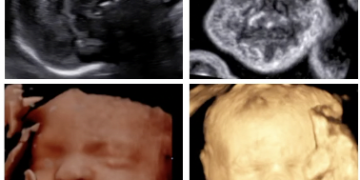

How To Do Giugno 2024: diagnosi e gestione delle anemie fetali

Cari soci, questo mese un nuovo video "How to do", dedicato alla diagnosi e alla gestione delle anemie fetali. Grazie a Tiziana Fanelli! Il video è accessibile ai soli soci...